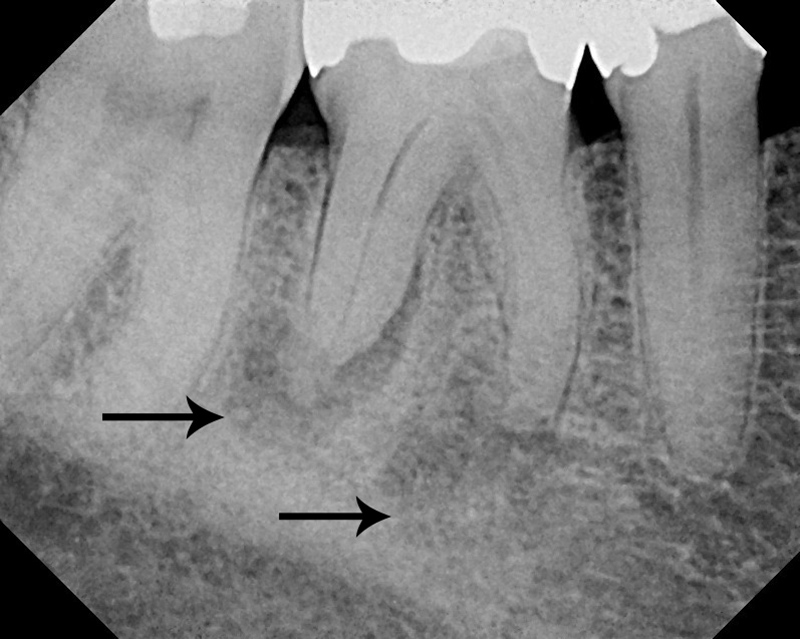

Periodontal abscess around the roots of the right first molar (arrows) in a 67-year old man. |

Periodontal abscess after root canal treatment. The arrows point to the opaque sealant used to seal the cleaned out root canal. |